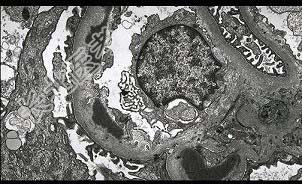

单项选择题阅读下列三张病理图片(图-1 Masson染色,图-2免疫荧光镜下IgG基膜内条带状沉积, 图-3电镜下基底膜有电子致密物沉积,这些基底膜内的暗色的电子致密物沉积常融合成肋骨样)可诊断哪种病理类型 ( )

E、膜增生性肾小球性肾炎Ⅱ型